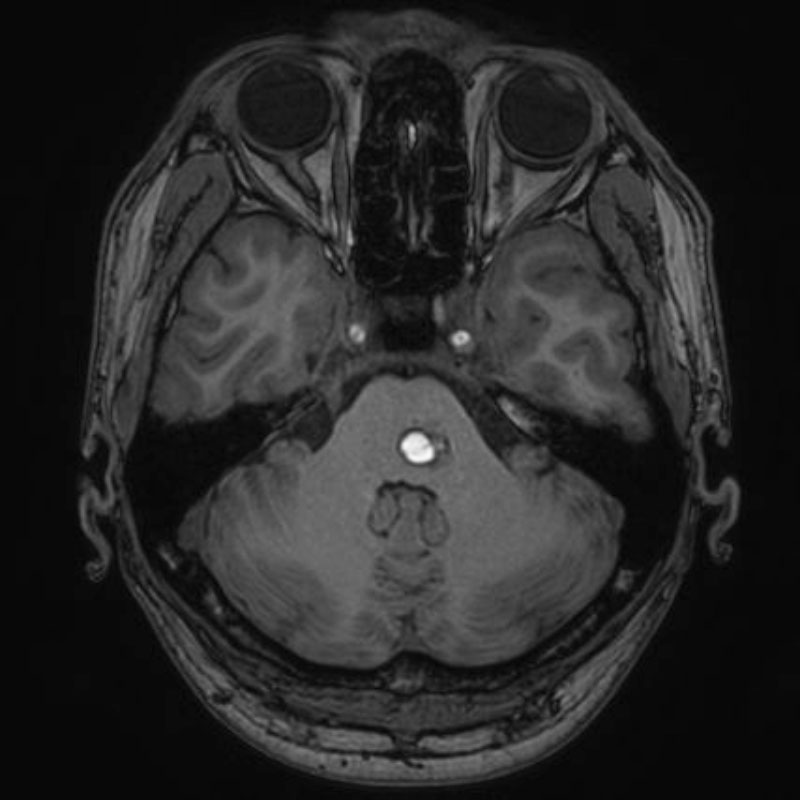

5月19日(火)

左内頚動脈狭窄症

経皮的頸動脈ステント留置術

住吉/木本